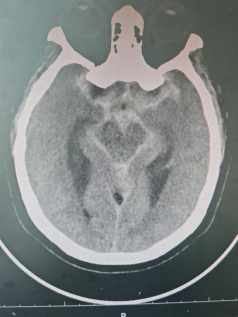

到达急诊科后,医护人员迅速对王大妈进行了初步检查。测量血压时,发现王大妈的血压高达235/121mmHg,远超正常范围(正常血压为90-139/60-89mmHg)。这一异常高的血压值立即引起了医护人员的警觉,并立即为王大妈安排了头颅CT检查。

头颅CT检查结果显示,王大妈存在蛛网膜下腔出血的情况。面对这一紧急情况,德安县总医院人民医院立即启动了神经外科会诊程序,组织专家团队对王大妈的病情进行了全面评估。经过专家们的会诊,王大妈被确诊为左侧大脑中动脉瘤,并需要尽快进行手术治疗。